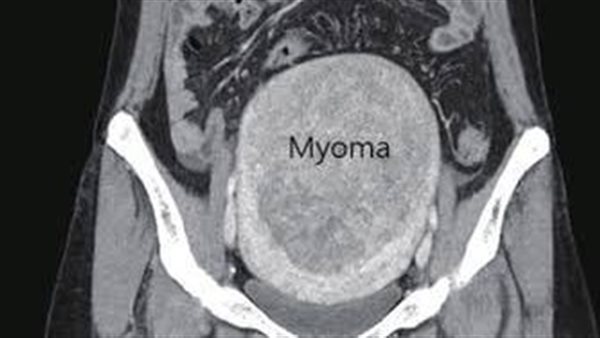

قال الدكتور أحمد سعفان، رئيس قسم الأشعة التداخلية بالمركز، إن المريضة التي تبلغ من العمر 32 عاما، جاءت إلى العيادة الخارجية للأشعة التداخلية، وكانت تعاني من ورم ليفي ضخم بالرحم، يعوق فرص الحمل، إلى جانب أنيميا حادة نتيجة نزيف مهبلي.